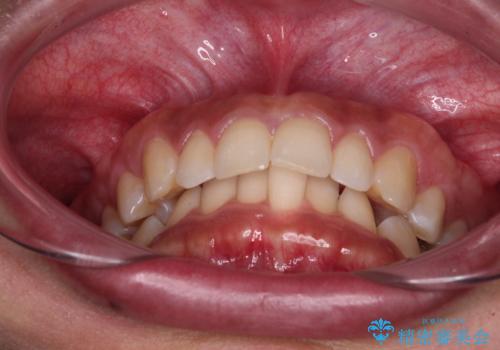

- 下顎前歯部には叢生が認められ、口を自然に閉じにくい状態でした。また、噛み合わせが深い「ディープバイト」の状態で、見た目だけでなく将来的な奥歯への負担も懸念されました。

口元の突出感を改善するため、上下左右の小臼歯4本を抜歯する矯正治療を計画しました。